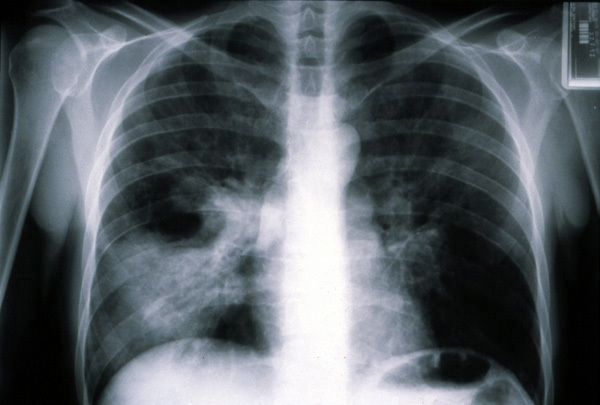

©La Revue du Praticien Radiographie de thorax de face. Pneumonie pneumococcique avec foyers alvéolaires multiples.